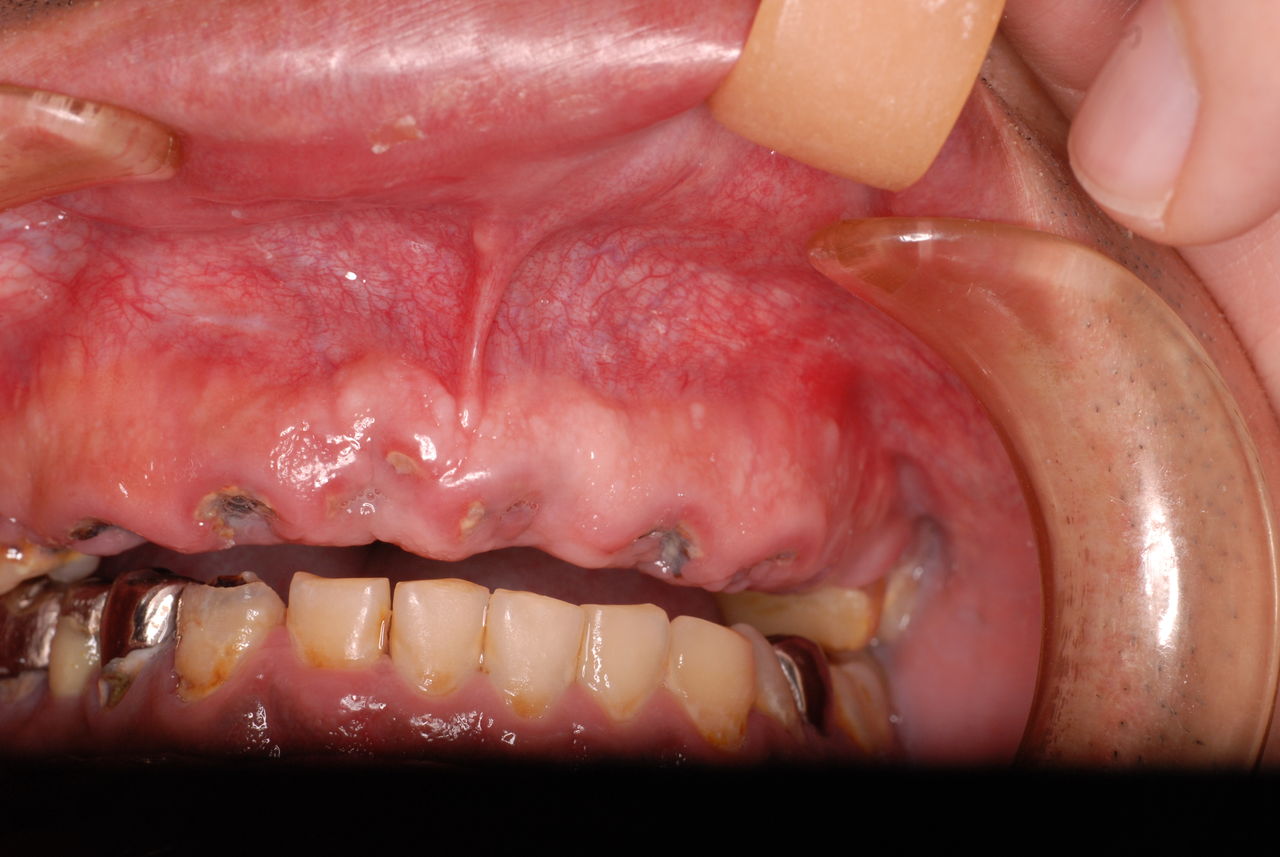

30代の男性の方です。

入れ歯を入れていました。歯科医院で歯を抜けず仕方なく入れ歯にしたとか。何とかならないものだったのか悔やまれました。

抜いた歯はありません。

一応差し歯にしましたが、歯茎の状態はよくはありません。

とりあえず希望を入れて差し歯にしたような感じです。